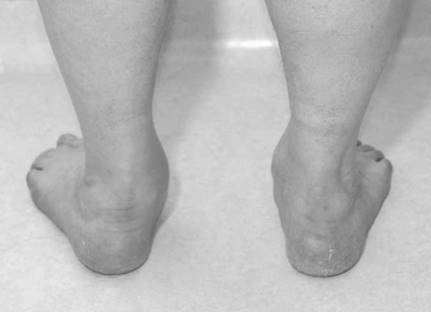

Illustration 2 for Ace FRCS Orthopaedics: Oxford University Press Adult Pathology Viva

Clinical Radiograph / Orthopedic Image

Reproduced from Raashid Luqmani, Theodore Pincus, and Maarten Boers, Rheumatoid Arthritis (Oxford Rheumatology Library), 2010, Figure 11.6, p.138, with permission from Oxford University Press.

This is a picture of a plano-valgus foot. There is the โ€˜too many toesโ€™ sign. Pes planus can be congenital or acquired. The commonest cause of adult acquired fl at foot is tibialis posterior tendon dysfunction (TPTD). The tibialis posterior is the main inverter of the hindfoot. It also acts as an elevator of the midfoot (sling) as it inserts into the navicular, plantar cuneiforms, and second, third, and fourth metatarsal (MT) bases.

The condition is most often seen in middle-aged women whose body morphology, aided by gravity, tests the tendon as it is starting to age.

The tendon can become infl amed, painful, and swollen. The foot does not initially change shape and patients are still able to do a single leg tiptoe raise, although they quickly fatigue (Johnson Stage 1). Some patients settle with enforced rest in a supportive brace or cast.

As the tendon degenerates it lengthens. The foot changes shape with the hindfoot going into valgus. Patients are no longer able to do a single leg tiptoe raise. (Often the pain over the tib post may have settled, especially if the tendon has completely ruptured.) If the hindfoot is still fl exible (Johnson Stage 2), this can be treated with orthotics to help support the foot and medial arch or by surgery. Surgery involves reinforcing the tibialis posterior tendon (TPT) with a fl exor digitorum longus (FDL) tendon transfer. This reconstruction is then protected by bringing the hindfoot into neutral alignment with a medial sliding calcaneal osteotomy. The Achilles tendon occasionally needs to be released (percutaneously), as if the hindfoot has been in valgus for some time it will have tightened preventing full correction to neutral.

I f the valgus hindfoot deformity is fi xed (Johnson Stage 3) reconstruction is not achievable. The subtalar joint is degenerate. Surgical treatments involve a talo-navicular and subtalar fusion or a formal triple arthrodesis.

M yerson added a fourth stage when the deformity led to signifi cant ankle arthritis secondary to valgus strain.